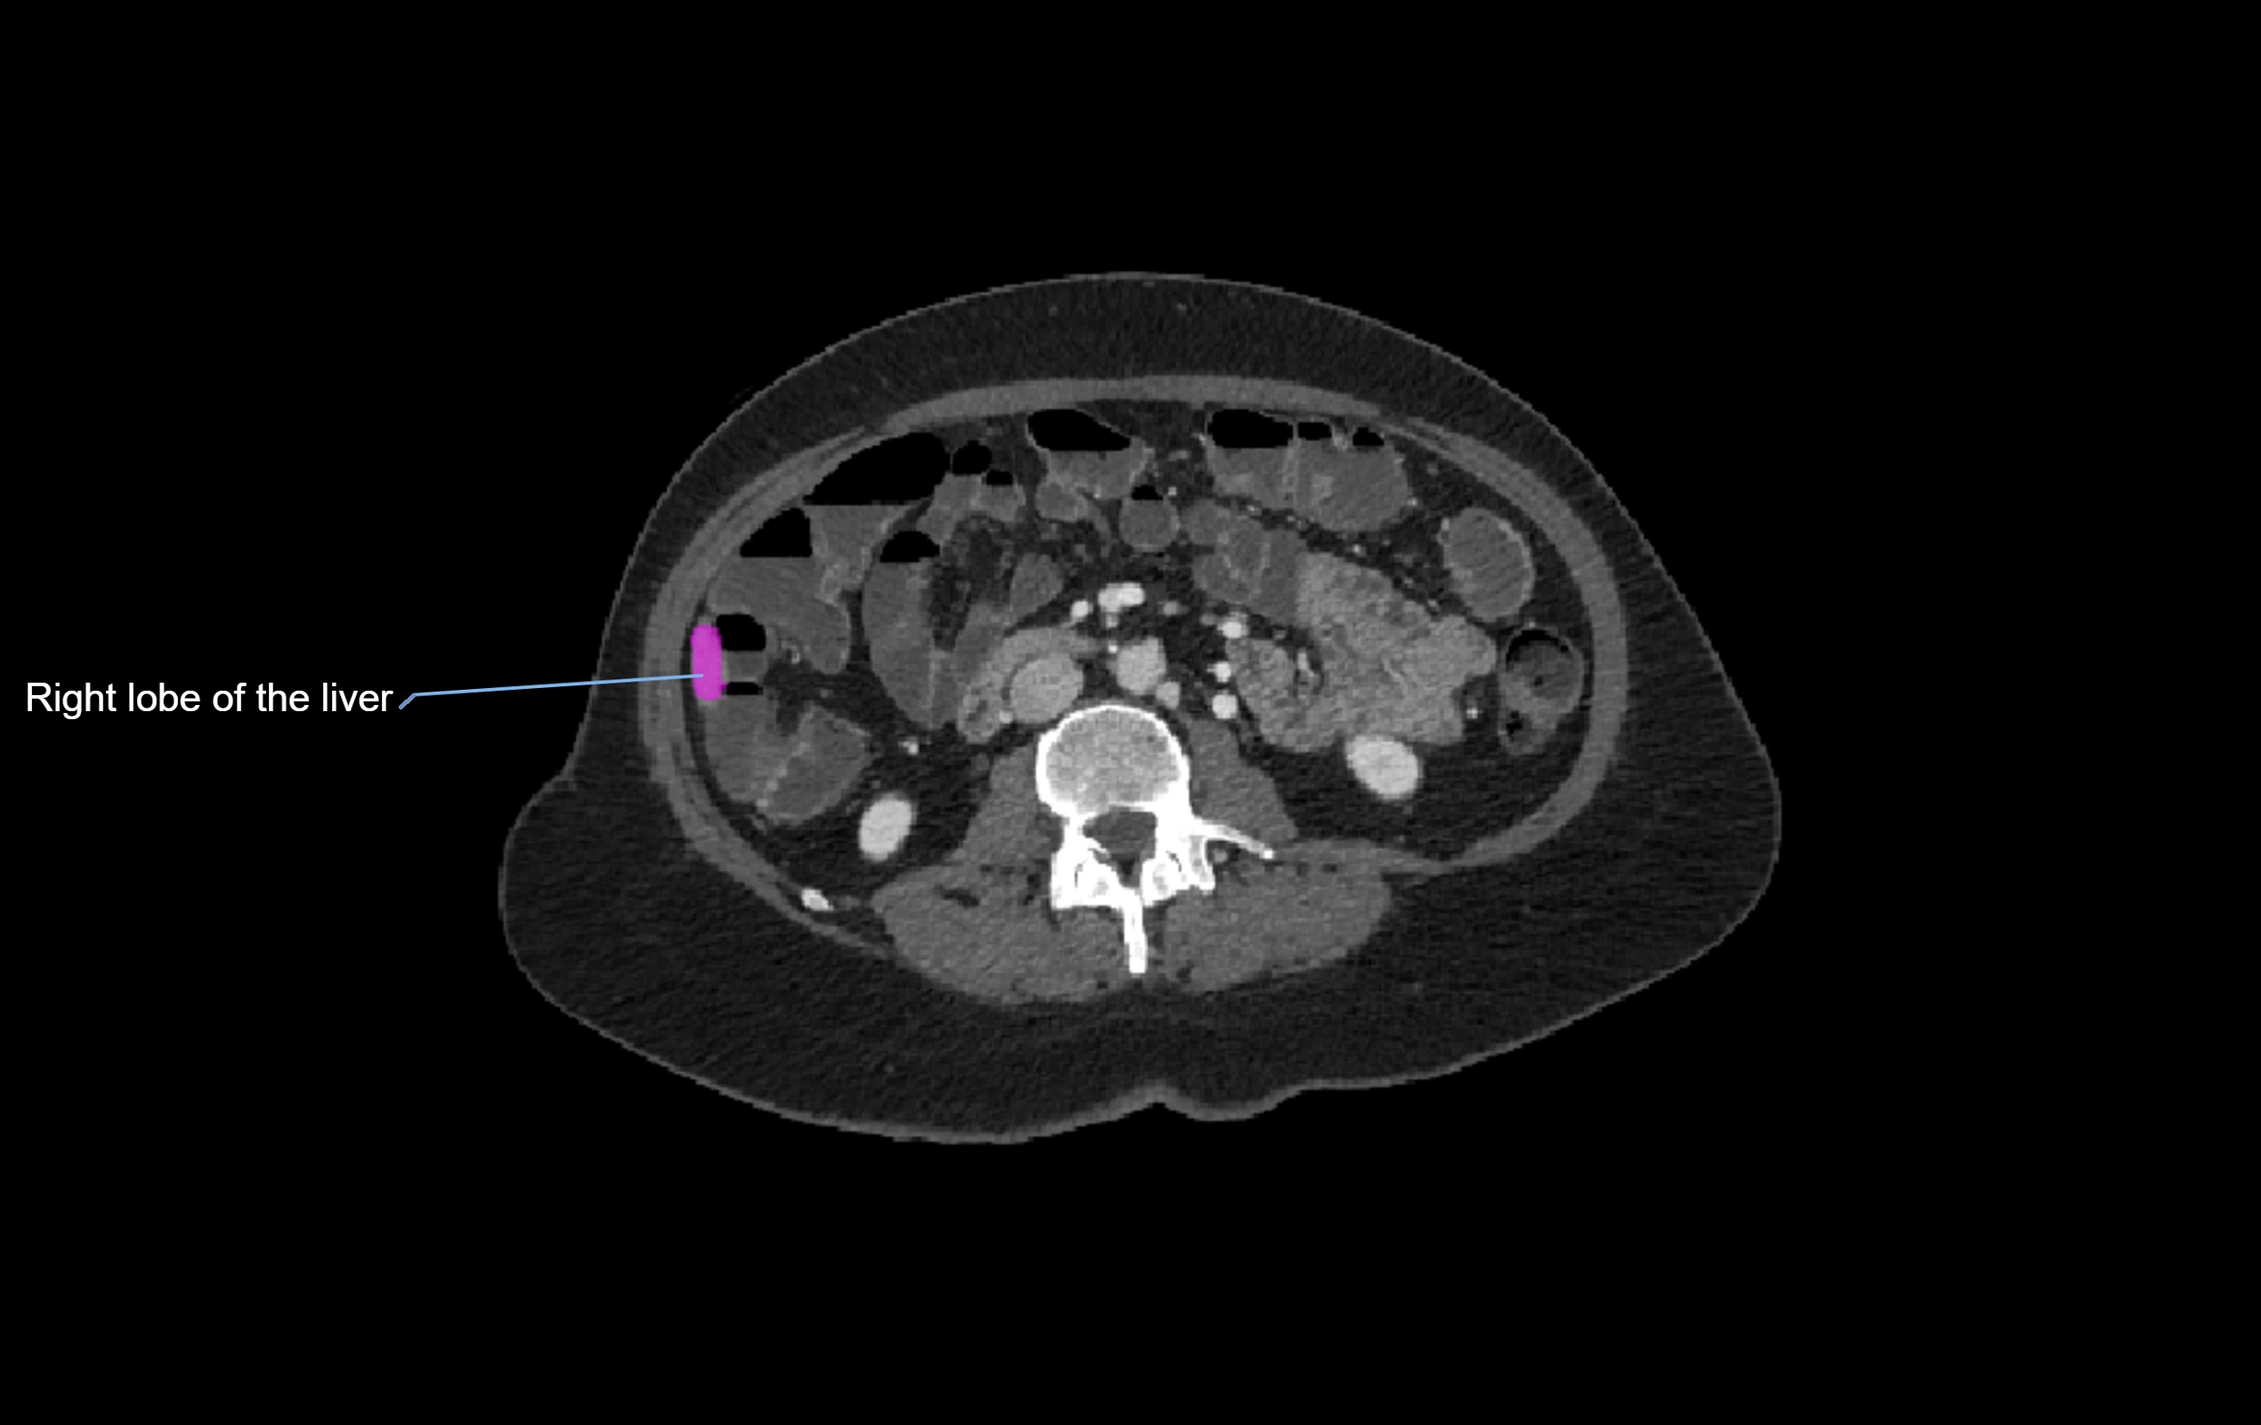

CT Image

image